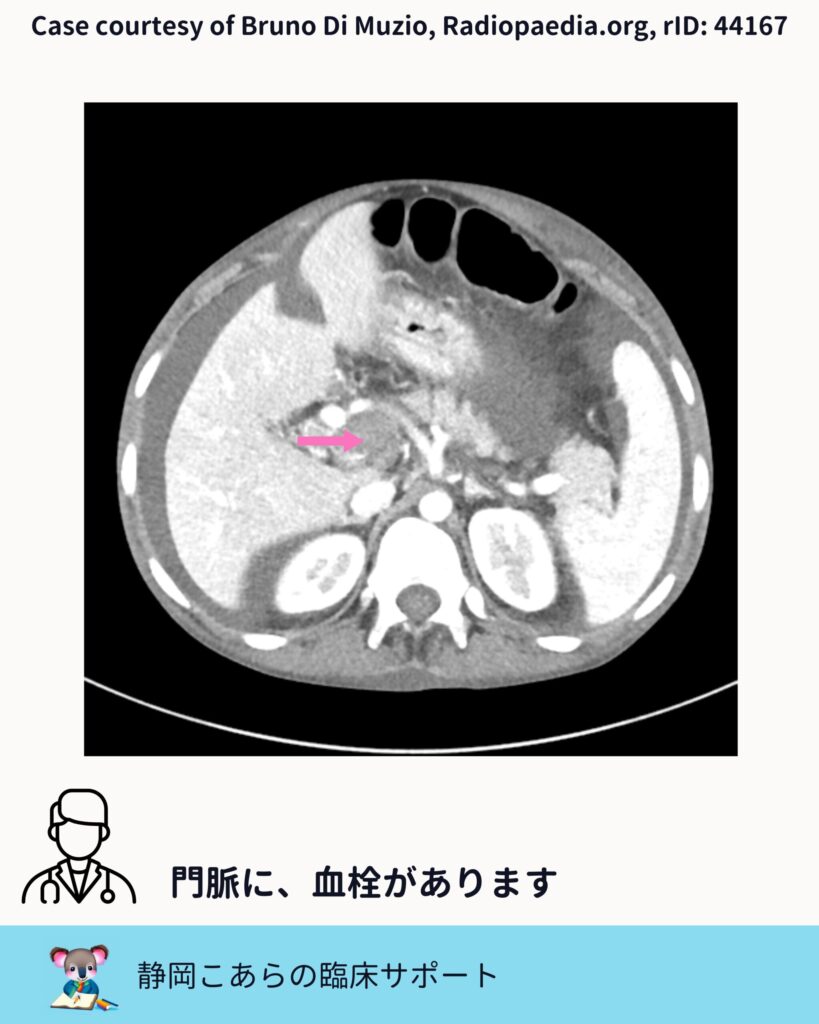

門脈血栓をどう見るか

今回の症例では、門脈内に造影欠損が認められます。スライスを追うと、はっきりとした血栓として確認できます。

門脈血栓症では、 ・門脈の拡張 ・造影欠損 ・側副血行路の有無

こうした点をセットで評価していくことが、臨床的には自然です。